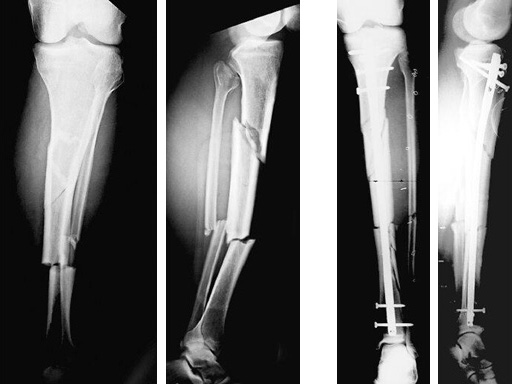

60-year-old man with a type II open 42-A2 fracture following a working accident.